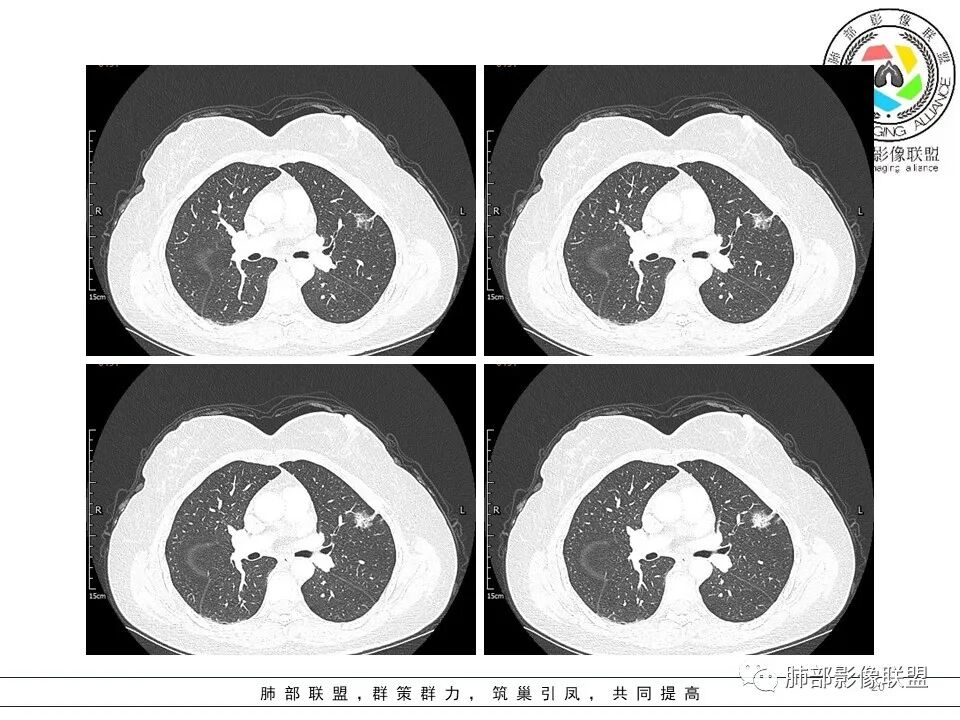

一.大结节影像特点:

左肺上叶胸膜下不规则结节影,分叶、粗短毛刺,胸膜牵拉等,像个“刺头”。

未见钙化,也未显示液化坏死或空洞。

与支气管相关,但取层未能显示支气管进入情况。

有几点应当引起我们高度重视:

1.病灶周围向几个方向膨出的边界清楚的磨玻璃影,这些磨玻璃影时隔几个月依然,几乎可以排除出血及一般的炎性改变。

2.病灶的胸膜牵拉线与其间病灶胸膜侧的磨玻璃边构成朝向胸壁的“月牙铲”结构,这种影像学表现某种程度上反映出病理学特征——病灶收缩+小叶间隔阻挡。

3.病灶实性密度区强化明显,这有助于我们区分一些其他类似病灶,如结核灶等!

4.邻近未见树芽征及卫星灶等。

结合临床,应当高度怀疑浸润性肺腺癌!